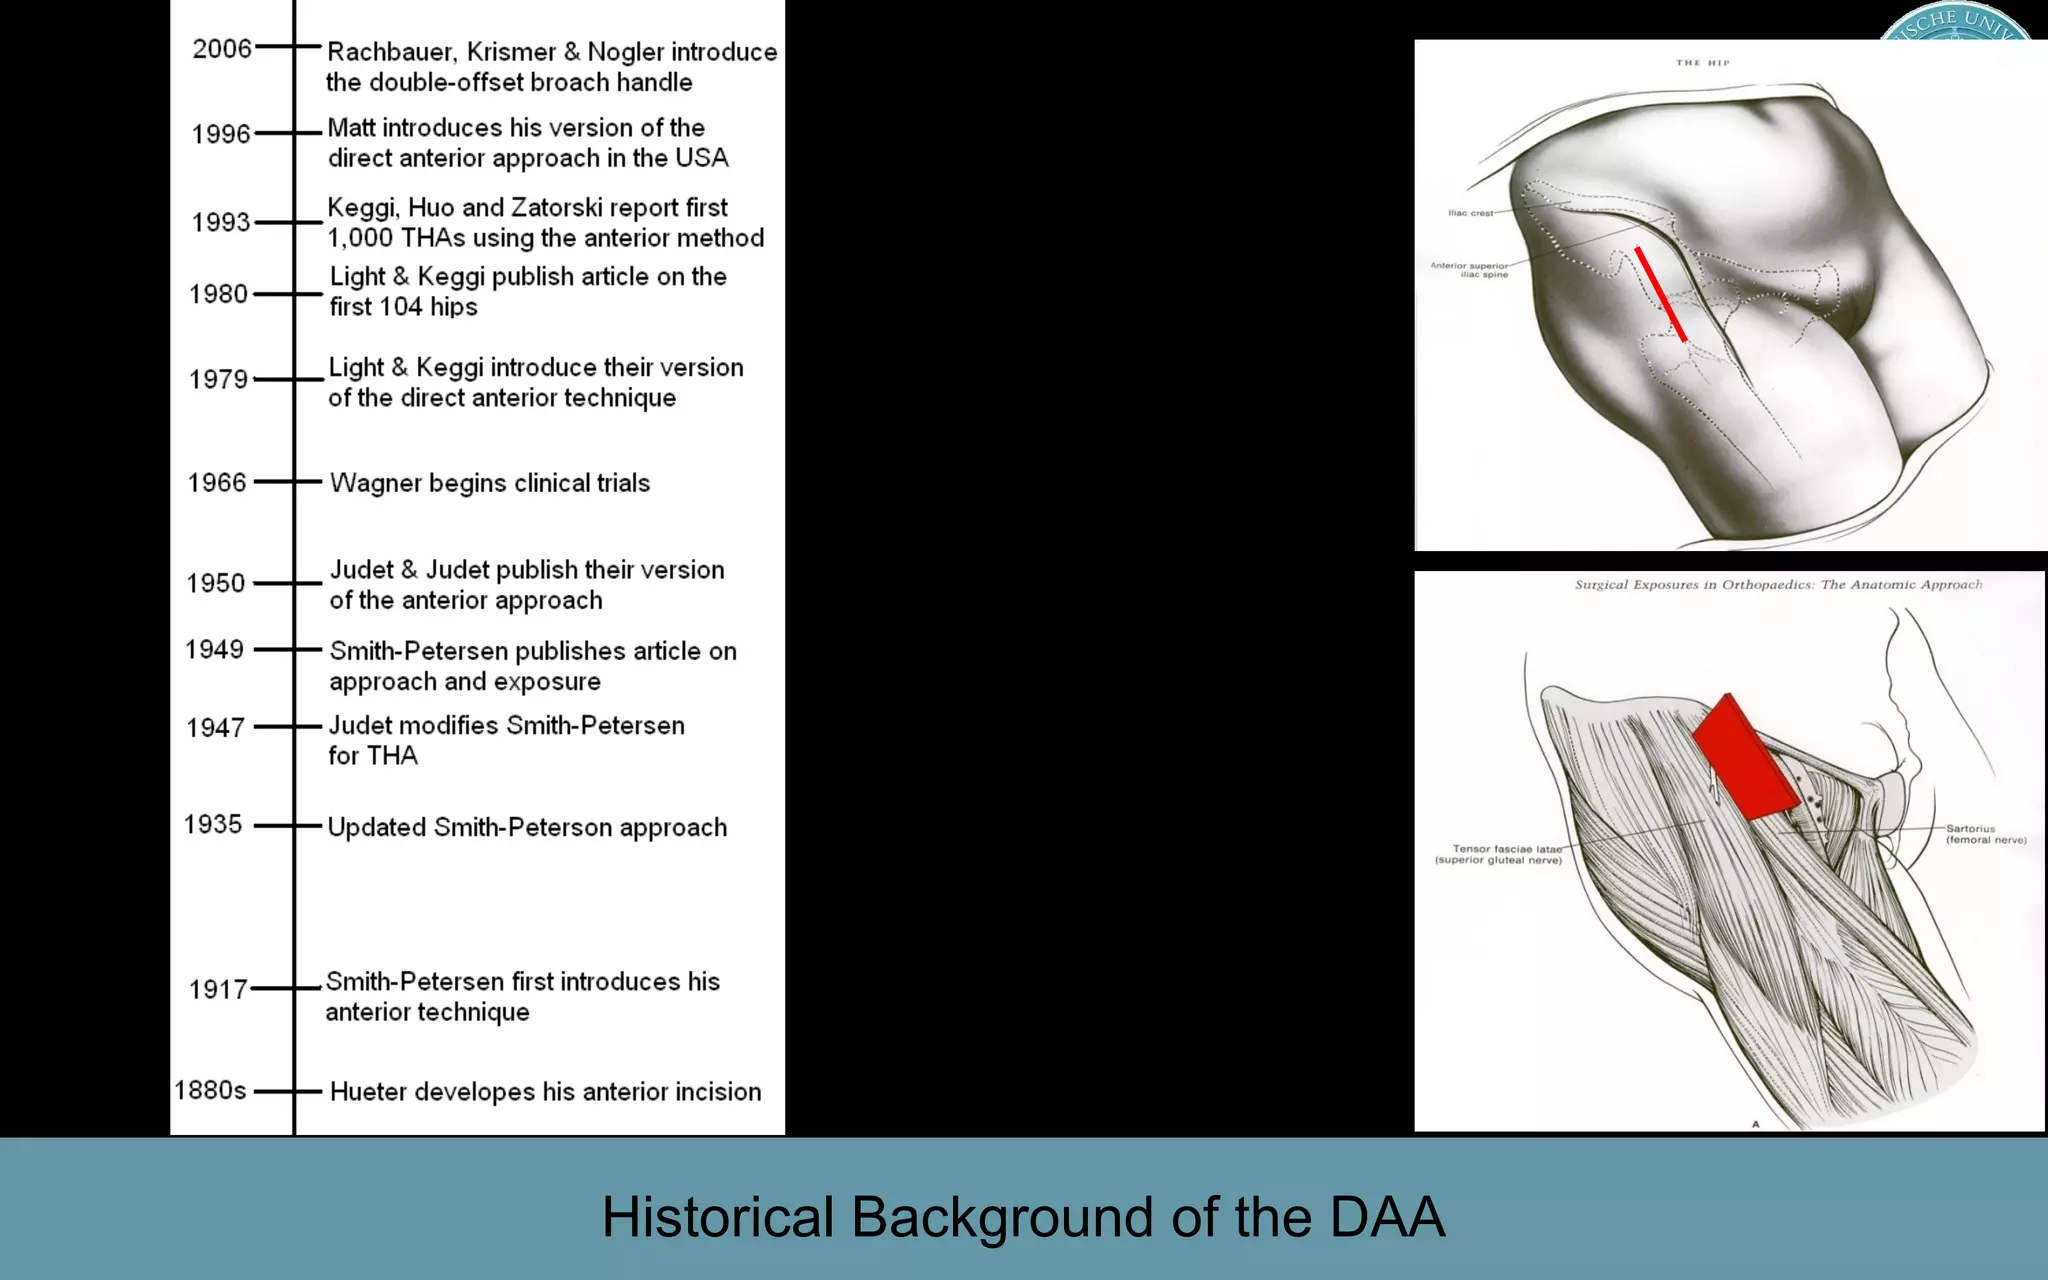

This document discusses the direct anterior approach for total hip arthroplasty. It lists advantages of the direct anterior approach such as increased stability, easier leg length equalization, lower costs by not requiring an operating table, reduced radiation exposure, faster rehabilitation, and lower risk of deep vein thrombosis. The document also discusses the historical background of the direct anterior approach, showing it has been performed since the 1880s. It presents images showing fatty degeneration of muscles and gluteal atrophy after total hip arthroplasty. Finally, it displays graphs comparing outcomes and improvements in quality of life domains between the direct anterior approach and minimally invasive approaches.